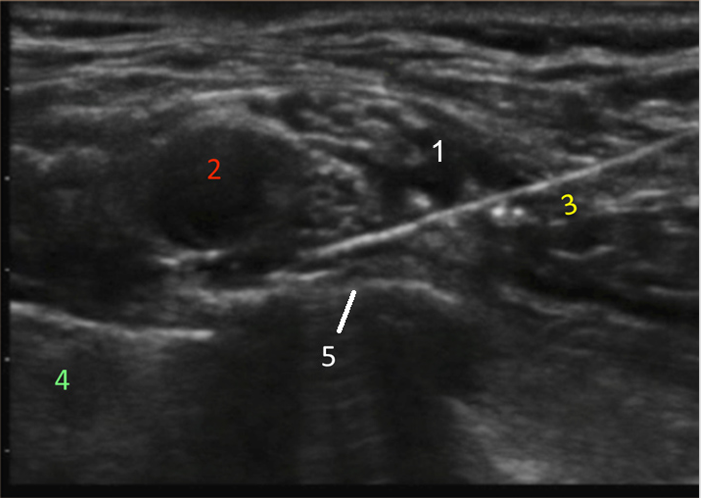

Supraclavicular Injection 1 Image

Brachial Plexus

Artery

Needle

Lung

Rib